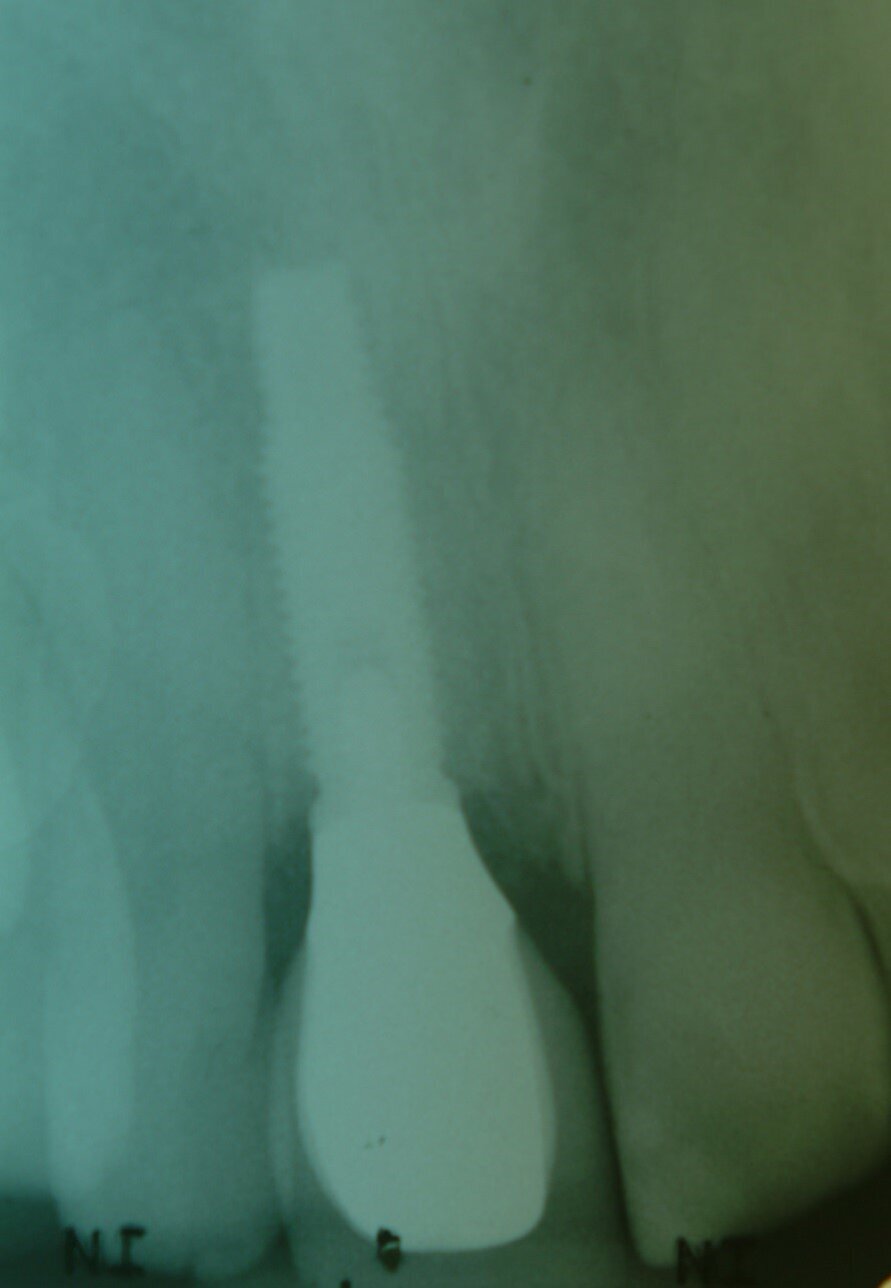

Patient RR was a healthy non-smoking 44 year old male who presented with a complaint of an unaesthetic upper right central incisor with extensive recession showing a large amount of darkened labial root surface. The situation was worsened by a high smile line and a porcelain crown contrasting dramatically with the root colour. He had had periodic swelling at the apical part of the recession over a long period. There was a history of trauma in his teens leading to root canal treatment and a crown, and subsequent apicectomy in his 20s. Clinical examination revealed an otherwise periodontally healthy, well looked-after mouth. (Fig. 1, 2, 3)

Diagnosis was of endodontic failure and possible root fracture leading to loss of labial bone and soft tissue.

2. Extraction and the split root confirmed (Fig. 4)